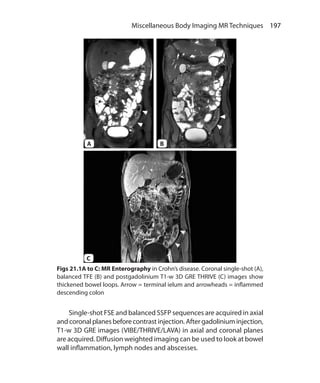

MR Techniques	 196

Magnetic Resonance Enterography	 196